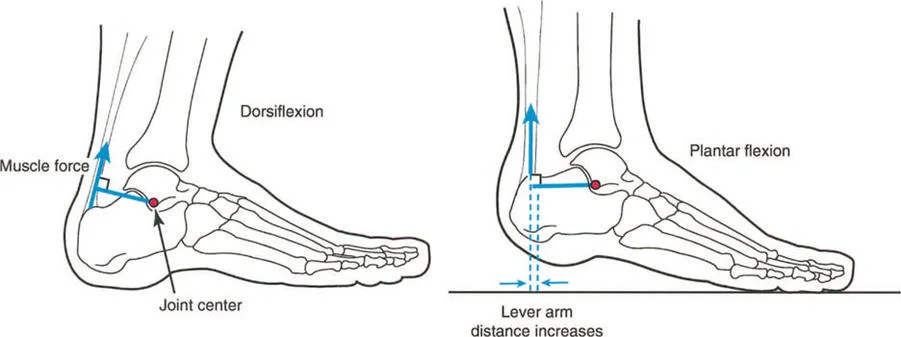

من الأمثلة السريرية الكلاسيكية للتشوه الديناميكي هو "حنف القدم الوظيفي" (Functional Equinus)، والذي يُرى غالبًا في حالات الشلل الدماغي أو التشنج بعد الإصابات. في وضع الفحص السريري الثابت، ومع ثني الركبة لإرخاء عضلة الساق (Gastrocnemius)، قد يكون المريض قادرًا تمامًا على ثني القدم ظهريًا بشكل سلبي (Dorsiflexion) لتتجاوز الوضع المحايد. ومع ذلك، أثناء مرحلة الوقوف على ساق واحدة في دورة المشي، تظل القدم في وضع حنف القدم المتيبس.

لماذا يحدث هذا؟ لأن الوقت المطلوب لتطبيق القوة العضلية للأعلى وثني القدم ظهريًا بنشاط يكون أكبر من المدة القصيرة لمرحلة الوقوف على ساق واحدة. غالبًا ما يتفاقم هذا بسبب التشنج الكامن، حيث تتغلب ردود الفعل الانعكاسية لوتر العرقوب (Achilles tendon) على العضلة الظنبوبية الأمامية (Anterior Tibialis).

أمثلة أخرى رئيسية للتشوهات الديناميكية تشمل "الورم الفخذي المفرط" (Severe Femoral Anteversion) و "الورك الأفحج" (Coxa Vara). في كلتا هاتين الشذوذات المعمارية، يتم تقصير الطول الفيزيائي لذراع الرافعة لعضلات المبعدة (Abductor muscles) بشكل مرضي بسبب التشوه العظمي نفسه. قد تكون عضلة الألوية الوسطى (Gluteus Medius) صحية تمامًا، ومعصبة جيدًا، وقادرة على توليد قوة بيولوجية طبيعية، لكنها تعاني من خلل وظيفي سريري عميق لأن ميزتها الميكانيكية قد سُلبت بسبب الهندسة الهيكلية المتغيرة. هذه الفئة الفرعية المحددة من الأمراض تُعرف باسم "تشوه في طول ذراع الرافعة".

بشكل خاص، يصف خلل وظيفة الذراع الرافعة حالة سريرية تتشوه فيها أذرع الرافعة الداخلية و/أو الخارجية بسبب سوء محاذاة العظام، أو التشوهات الالتوائية، أو تيبسات المفاصل الموضعية.

بمجرد أن يبدأ الجراح في التفكير من حيث "العزوم" التي تولد القوة، بدلاً من مجرد انقباض عضلي معزول، فإنه يبدأ تلقائيًا في فحص النصف الآخر من المعادلة الميكانيكية: الرافعة نفسها.

بينما لا يستطيع الطب الحديث فعل الكثير لزيادة القوة البيولوجية الخام التي تولدها العضلة بشكل دائم (بخلاف العلاج الطبيعي)، يمكن غالبًا زيادة حجم العزم المؤثر على المفصل بشكل كبير ببساطة عن طريق تصحيح خلل وظيفة الذراع الرافعة جراحيًا. هذا هو جوهر النهج الذي يتبعه الأستاذ الدكتور محمد هطيف في علاج التشوهات العظمية المعقدة، حيث يركز على استعادة الميكانيكا الحيوية السليمة للجسم.